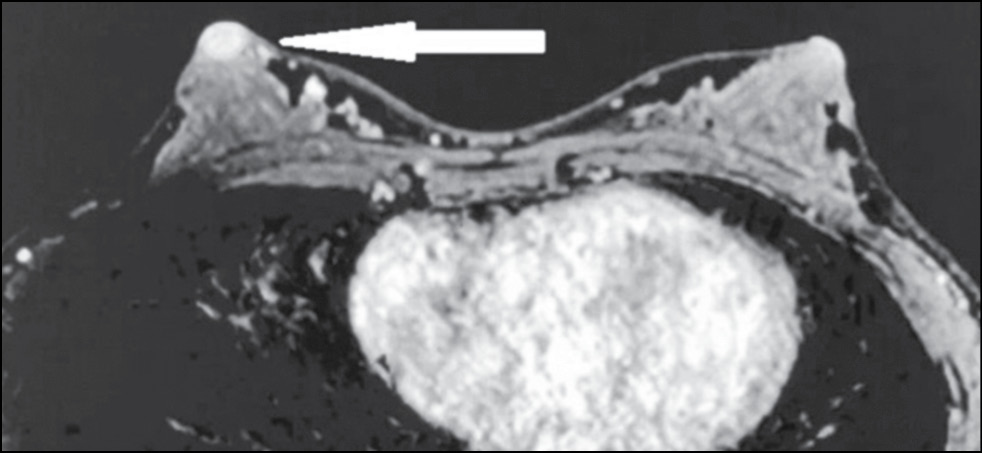

In a 43-year-old patient who had no complaints, the breast was examined by MRI to assess the integrity of implants. The asymmetric enhancement of the left nipple was accidentally found (Figs. 9 and 10). Three-year dynamic observation did not reveal any unfavorable changes.

Figure 9. Magnetic resonance imaging (early postcontrast series): asymmetric contrast accumulation in the left nipple; normal finding (arrow).

Figure 10. Magnetic resonance imaging (MIP): asymmetric contrast accumulation in the left nipple; normal finding (arrow).

Cases 3 and 4 prove that asymmetric contrast accumulation in MRI is not necessarily a sign of pathology. Normally, in MRI, both nipples accumulate the contrast agent at the same rate and intensity. However, nipple asymmetry may be the normal variation. Possible reasons include special NAC anatomy, breast size, breast compression and friction with clothing, blood flow variations, and local inflammation. [12] Aome physiological features and differences are involved in contrast accumulation in NAC structures. Both breasts usually show symmetrical thin rings of enhancement. In some cases, enhancement is asymmetrical in the early phase and becomes symmetrical in later phases. In a study of 530 normal nipples in 265 asymptomatic women, Gao et al. used T1-weighted NAC images to describe three areas of enhancement. [12]

Nipple inversion is a benign condition associated with the insufficient ability of the mesenchymal tissue to fix the nipple in the right position. [12] It occurs in 4% of women and men. Nipples are convex in 75% of women, flat in 23%, and inverted in 2%. MIP images are well suited for assessing the morphology and symmetry of the NAC. On postcontrast images, the nipple should be hypo- or isointense compared with the enhanced parenchymal tissue in the background. [12]